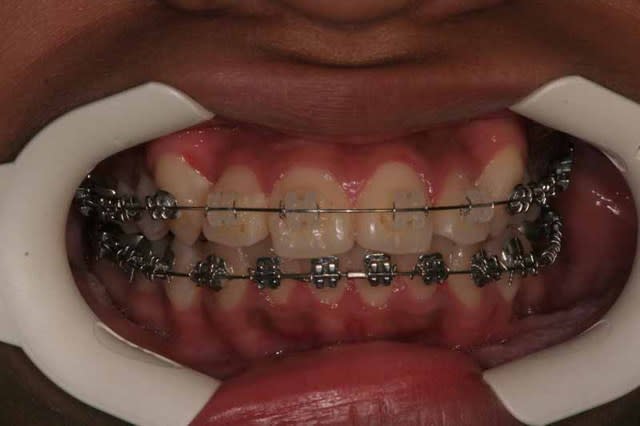

16/02/2007 à 21h38

Bonsoir,

"Tant que j'y pense, si on change les brackets et on met du Demon, ca va se faire tout seul, avec un petit grain de NiTi en .014, une pincee de croissance, on laisse mijoter jusqu'a l'age de 18 ans et voila le cas est fait...

Soyons serieux..."

14 mois séparent les photos.

@+ Bjc.

Img 1 0477 gllgih - Eugenol

Img 2 3340 zl3qii - Eugenol

Img 3 9221 ghe6th - Eugenol